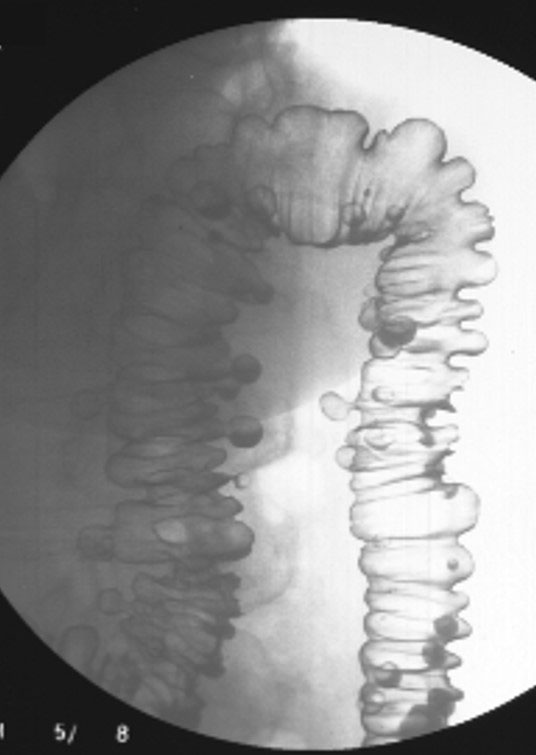

What are diverticula?

Outpouchings (herniations) of the mucosal layer through a weakened muscular layer of the bowel wall.

What is diverticulosis?

The presence of diverticula without inflammation.

Where do diverticula most commonly occur?

The sigmoid colon.

Do diverticula usually occur singly or in groups?

In groups, not singly.